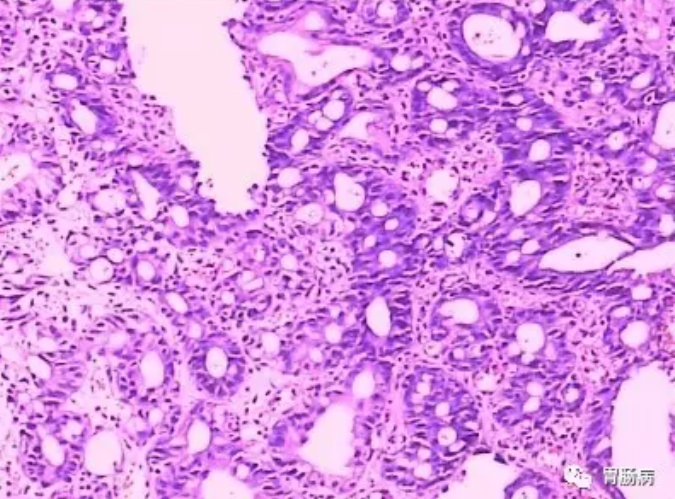

图2 异型增生病理图片

异型增生可分为腺瘤型、隐窝型、再生型、异型性囊性扩张型及球型增生等。

是指明确的肿瘤性非浸润性上皮。当异型增生上皮形成扁平病变,称为胃上皮异型增生;

当异型增生上皮形成隆起性病变则称之为“腺瘤”;

按照异型增生分化程度和范围分为轻、中、重三级,

即轻度是指炎症性及再生性良性异型增生病变;

中度是指异型化较为明显,接近胃癌的“临界性病变”;

重度是指异型化更为明显,形态上难以和分化型癌相区别的异型增生。